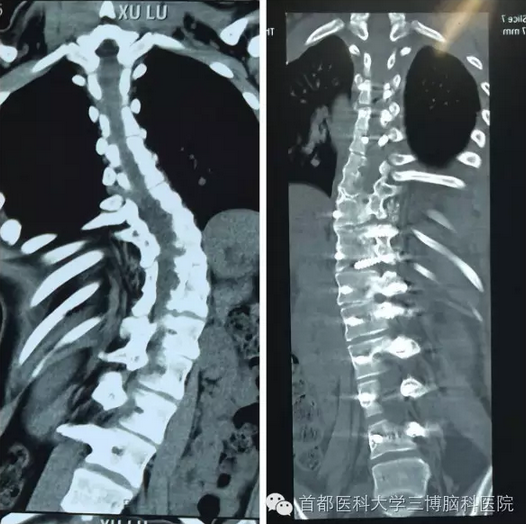

术前术后三维CT对比图

范涛教授了解孩子的具体情况后,一边安排助手帮患者向基金会提出援助申请,一边研究手术方案。基金会了解和审核患者情况后,为璐璐提供了5万元的资助。范涛教授按计划在全程神经电生理监测下为璐璐做了脊髓栓系松解术和脊柱侧弯矫正手术。手术非常成功,范教授用20枚螺钉矫正了她严重侧弯的脊椎,并且完好保护了脊髓和神经,术后璐璐肢体活动自如,无任何并发症。

术前术后CT对比图